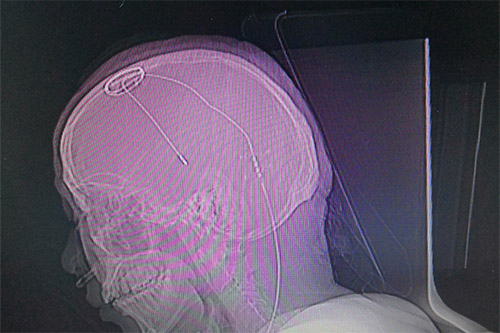

▲患者植入脑起搏器后的影像图

电极到达预定位置后,刘伟钦主任对患者进行感觉和运动测试,以直观地评估电极工作情况。患者说话清晰,视力视觉无影响,四肢活动自如,手脚抖动消失,手术效果令人满意,然后对电极位置进行固定。随后对患者进行全身麻醉,将导线经过耳后皮下隧道与置于锁骨下皮下的电池连接固定。术后行CT扫描,将CT扫描数据导入手术计划系统融合、计算,电极与预设手术路径完全吻合,位置准确无误,手术无出血,手术顺利完成。

准备就绪后,医生利用磁共振(MR)结合立体定向设备为患者进行影像扫描,再利用手术计划系统进行数据计算,规划手术路径,确定手术的三维立体精准坐标。“电极的直径只有1毫米左右,对手术定位精准度要求非常高,哪怕一点误差都会影响治疗效果。”将手术坐标与患者头部定位支架核对确定后,刘伟钦主任及其团队在患者头部切开了一道切口,并在颅骨打孔,固定好电极基环,最后将电极缓缓植入大脑内丘脑底核处。